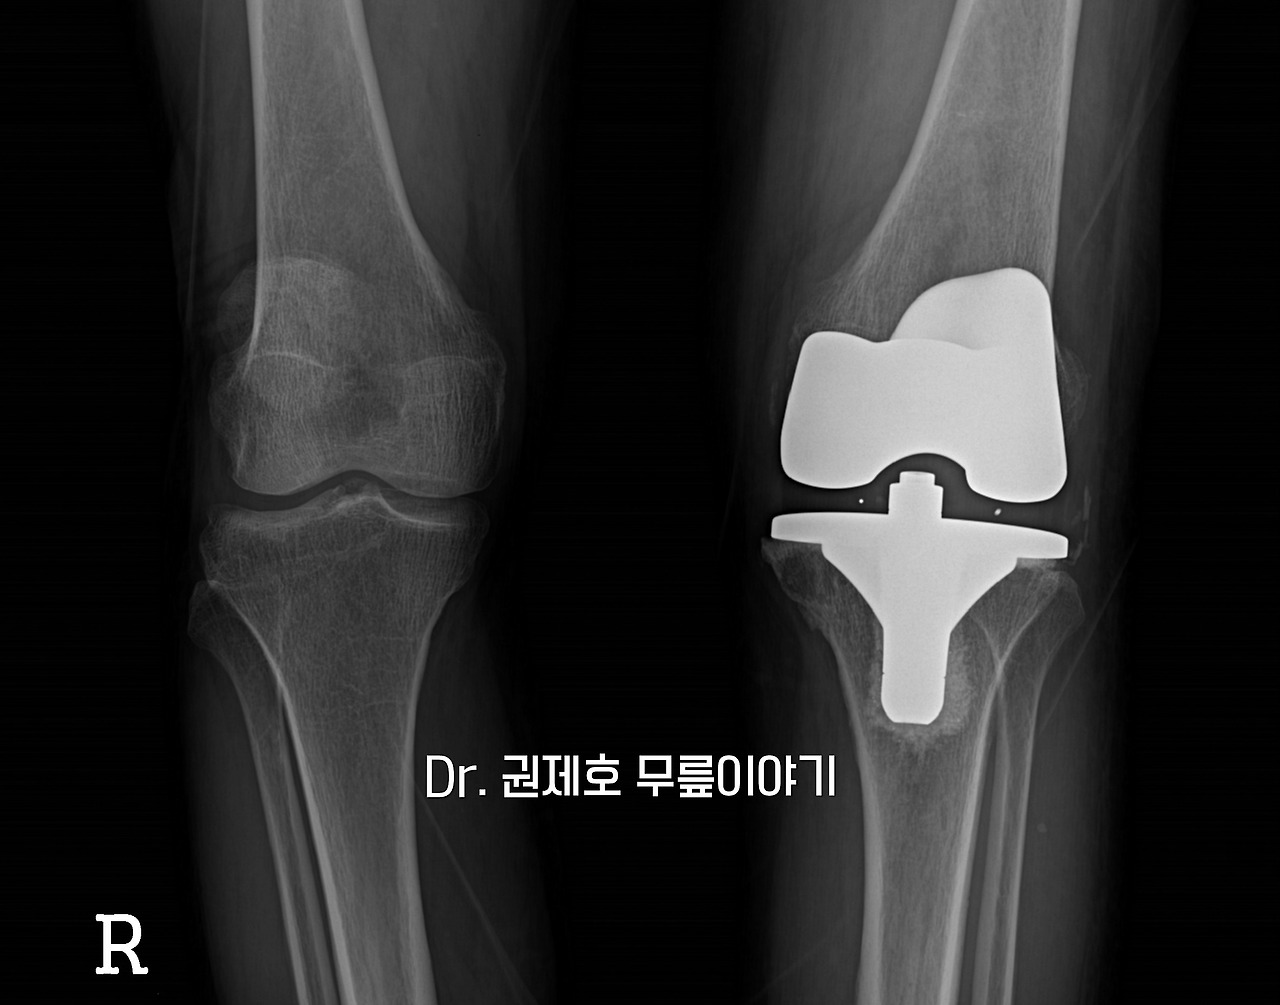

X선 검사를 시행했다. 무릎 차렷 한 상태에서 앞에서 보는 검사이다. 사진에서 보면 왼쪽 무릎에 안쪽 관절 간격이 없어져 붙어버린 소견을 확인할 수 있다.

수술은 비교적 빠르게 시행된다. 닮아 없어진 연골을 모두 제거하고 코발트크롬으로 만들어진 인공관절로 닳은 관절을 교체하게 된다. 이 과정에서 하지 정렬 즉, 다리의 열도 같이 맞춰줘야 하며, 관절의 간격도 맞춰야 하는 복잡한 이론이 적용된다. 수술하면서 이 모든 것을 고려해가면서 퇴행성관절염 수술을 한다.

2주 정도가 지나면 자력을 서있을 수 있다. 실을 제거하고 나서 다시 사진을 검사한다.

로젠버그 사진도 촬영한다. 관절을 대신하는 인공관절의 모습과 뼈와 잘 어우러졌는지 그리고 연골을 대신하는 bearing의 위치도 확인하게 된다.

관절염으로 휜다리가 있는 다리가 인공관절 후 반듯해진 모습을 확인할 수 있다.